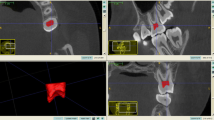

The present study aimed to investigate the performance of a Bayesian method in the evaluation of dental age-related evidence collected by means of a geometrical approximation procedure of the pulp chamber volume. Measurement of this volume was based on three-dimensional cone beam computed tomography images.

Pinchi V, Pradella F, Buti J, Baldinotti C, Focardi M, Norelli G-A (2015) A new age estimation procedure based on the 3D CBCT study of the pulp cavity and hard tissues of the teeth for forensic purposes: a pilot study. J Forensic Legal Med 36:150–157. https://doi.org/10.1016/j.jflm.2015.09.015

Ge Z-p, Ma R-h, Li G, Zhang J-z, Ma X-c (2015) Age estimation based on pulp chamber volume of first molars from cone-beam computed tomography images. Forensic Sci Int 253:133 e131–133.e137

Z-p G, Yang P, Li G, Zhang J-z, Ma X-c (2016) Age estimation based on pulp cavity/chamber volume of 13 types of tooth from cone beam computed tomography images. Int J Legal Med 130:1159–1167